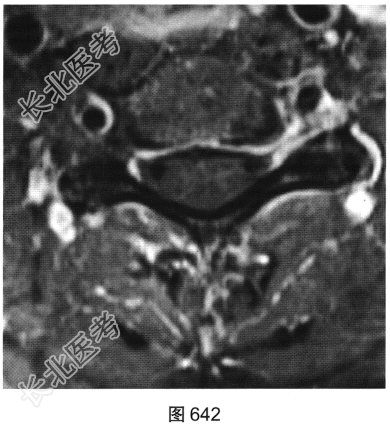

- 多项选择题3.[提示]患者保守治疗2个月后复查MRI,见图638~图642。复查的MRI图像与前次比较, 有哪些影像学变化( )

A、病变明显变小

B、颈前软组织强化

C、增强后未见强化

D、增强后可见小片状强化

E、C

间盘信号有变化F、硬膜囊及颈髓受压缓解

关注下方微信公众号,搜题查看答案

- 多项选择题4.根据复查的MRI表现,该患者可能的诊断是( )